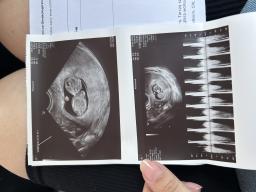

Dziewczyny byłam wczoraj na USG.. ze strachu. Nawet myślałam o detektorze tętna ale stwierdziłam że wolę co tydzień chodzić na USG niż to.. i na szczęście wszystko jest dobrze. To już mały człowieczek. Mój Syn jak go zobaczył to powiedział: mamo, on do mnie macha 👋 🥹

https://zapodaj.net/plik-pyoRonkHnv